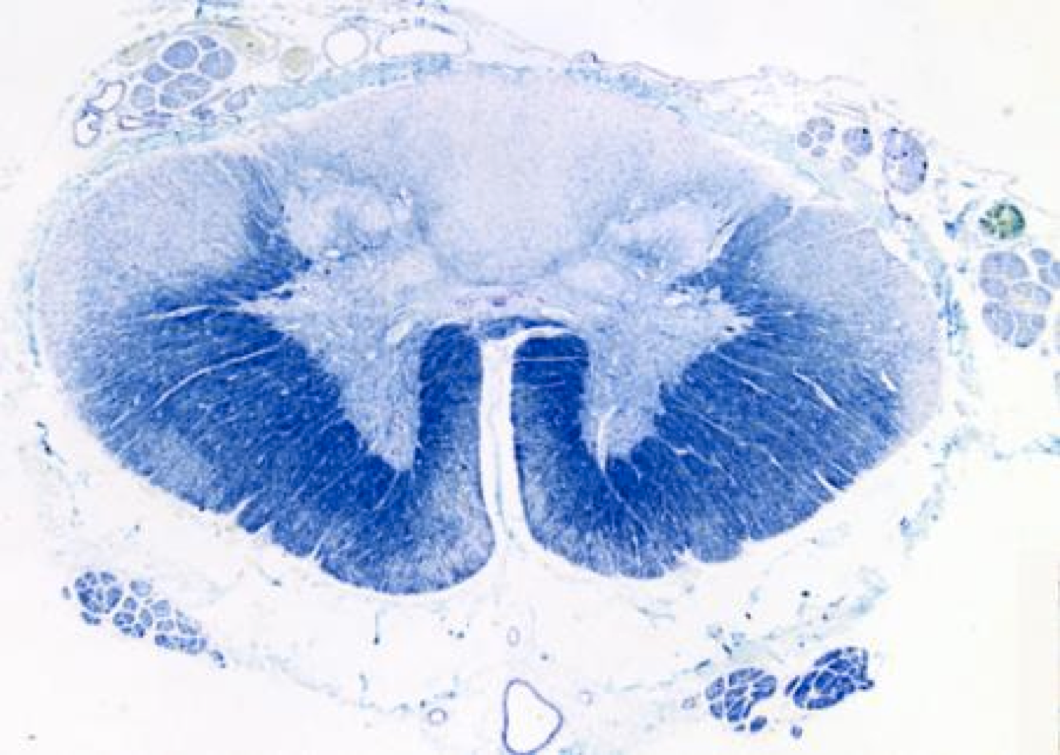

Friedrich’s ataxia: tract degeneration - Dorsal columns, spinocerebellar tracts, lateral corticospinal tracts and DRG

Most common hereditary ataxia

AR, Chromosome 9, Triplet repeat GAA, Frataxin

50% hypertrophic cardiomyopathy, severe scoliosis